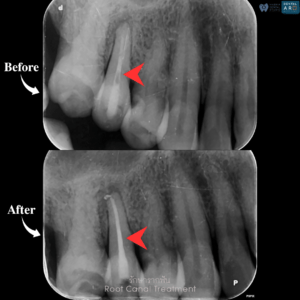

รักษารากฟัน

คือ การรักษาฟันที่เกิดการอักเสบและติดเชื้อภายในโพรงประสาทฟัน และเนื้อเยื่อรอบปลายรากฟัน อันมีสาเหตุมาการอักเสบและติดเชื้อภายในรากฟัน โดยทันตแพทย์จะทำการทำความสะอาดและใส่ยาในคลองรากฟัน และทำการอุดรากฟันเป็นขั้นตอนสุดท้าย การรักษารากฟันจะช่วยเก็บรักษาฟันให้สามารถคงอยู่ในช่องปากต่อได้ โดยไม่ต้องถอนฟันและไม่ต้องใส่ฟันทดแทน